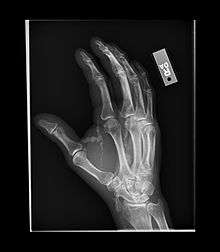

Tumoral calcinosis is a rare condition in which there is calcium deposition in the soft tissue in periarticular location i.e. around joints.[1] The accumulations are outside the joint capsule. They are frequently seen in patients undergoing renal dialysis. It is also considered by some to have a hereditary predisposition. The name indicates calcinosis (calcium deposition) which resembles tumor (like a new growth). They are not true neoplasms - they don't have dividing cells. They are just deposition of inorganic calcium with serum exudate. Children and adolescents (6 to 25 years) are the most commonly affected. The symptom that the accumulations cause is not pain but swelling around joints. They have propensity to enlarge progressively and ulcerate the overlying skin and extrude. They are most common around shoulders, hips and elbows. Laboratory evaluation reveal normal serum calcium levels and hyperphosphatemia. Rarely ALP (alkaline phosphatase - an enzyme active at sites of bone formation) may be elevated. Treatment is normalization of serum phosphate levels and resection of lesion. Surgical removal should be complete and if part of it is left, there is inevitable recurrence. Cutting through the excised calcium deposition reveals semifluid calcium suspension in albumin encapsulated by fibrous tissue.